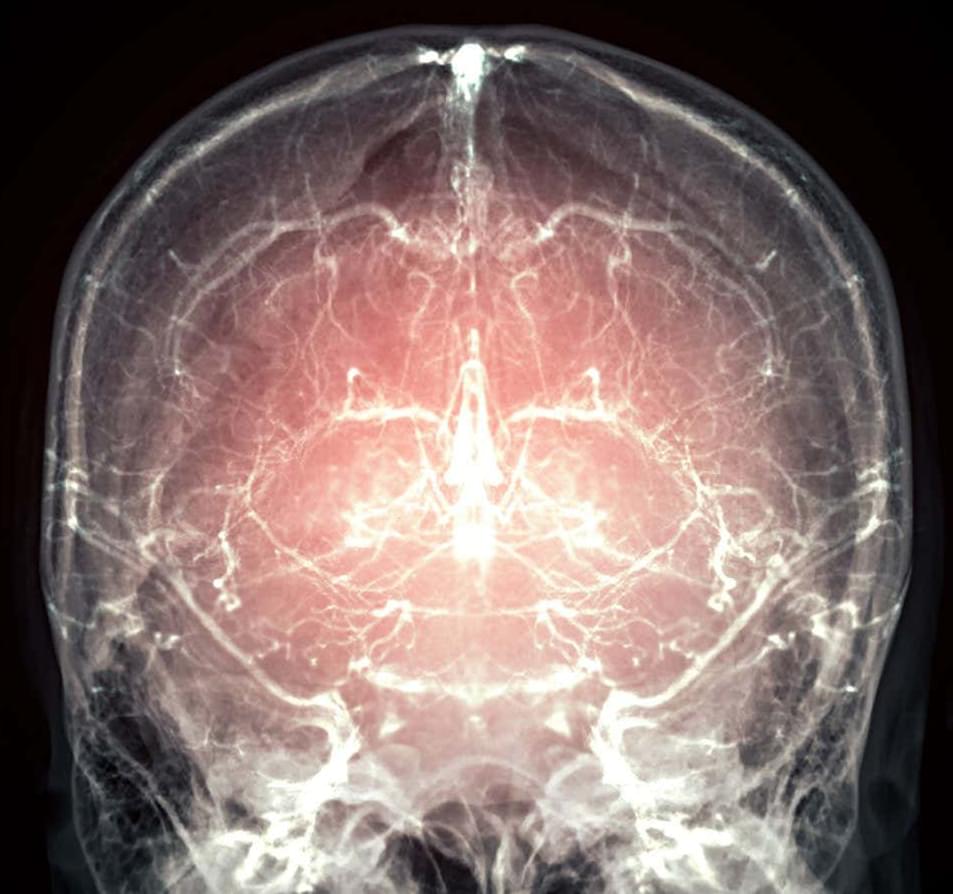

Both women with preeclampsia and gestational hypertension experience high blood pressure during pregnancy that frequently persists post partum.28 Lower white matter integrity has been reported from the peripartum period into later life.3,12,29 Hypertension-related white matter injury30,31 is associated with slower processing speed, executive dysfunction, and memory impairment.31 Although cognitive impact may not be obvious in the early postpartum period, white matter changes predict later cognitive decline and dementia,32 and converging longitudinal evidence suggests that reductions in white matter volume and integrity track cognitive decline, supporting the interpretation that better-preserved white matter is beneficial.33